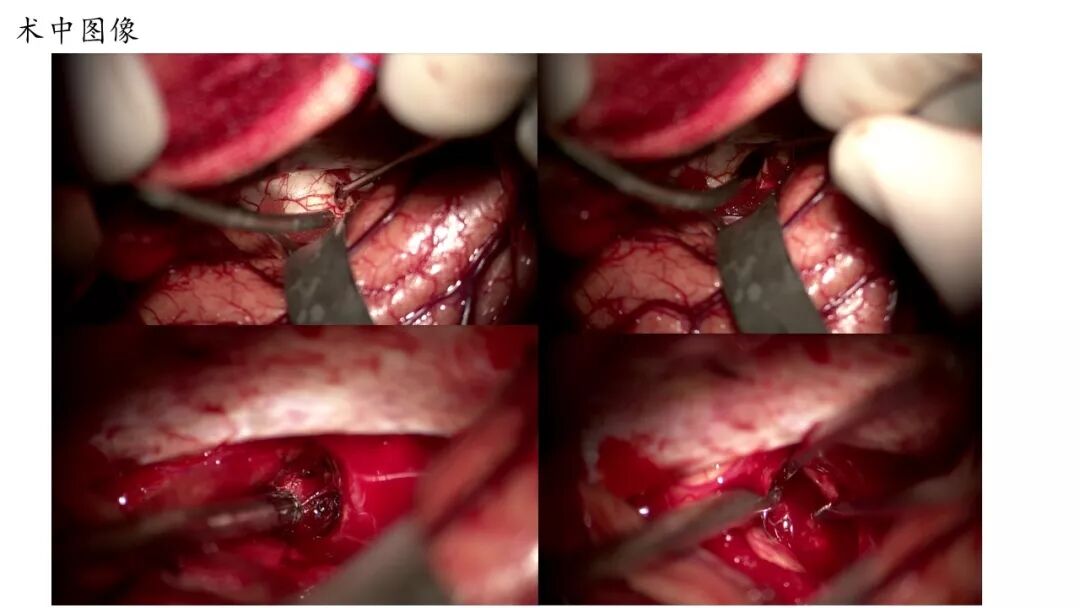

今天为大家分享的是《贝朗时间》第五十一期,由河南省人民医院神经外科步星耀教授团队带来的:脑干海绵状血管瘤伴出血手术病例分享,欢迎阅读、分享!